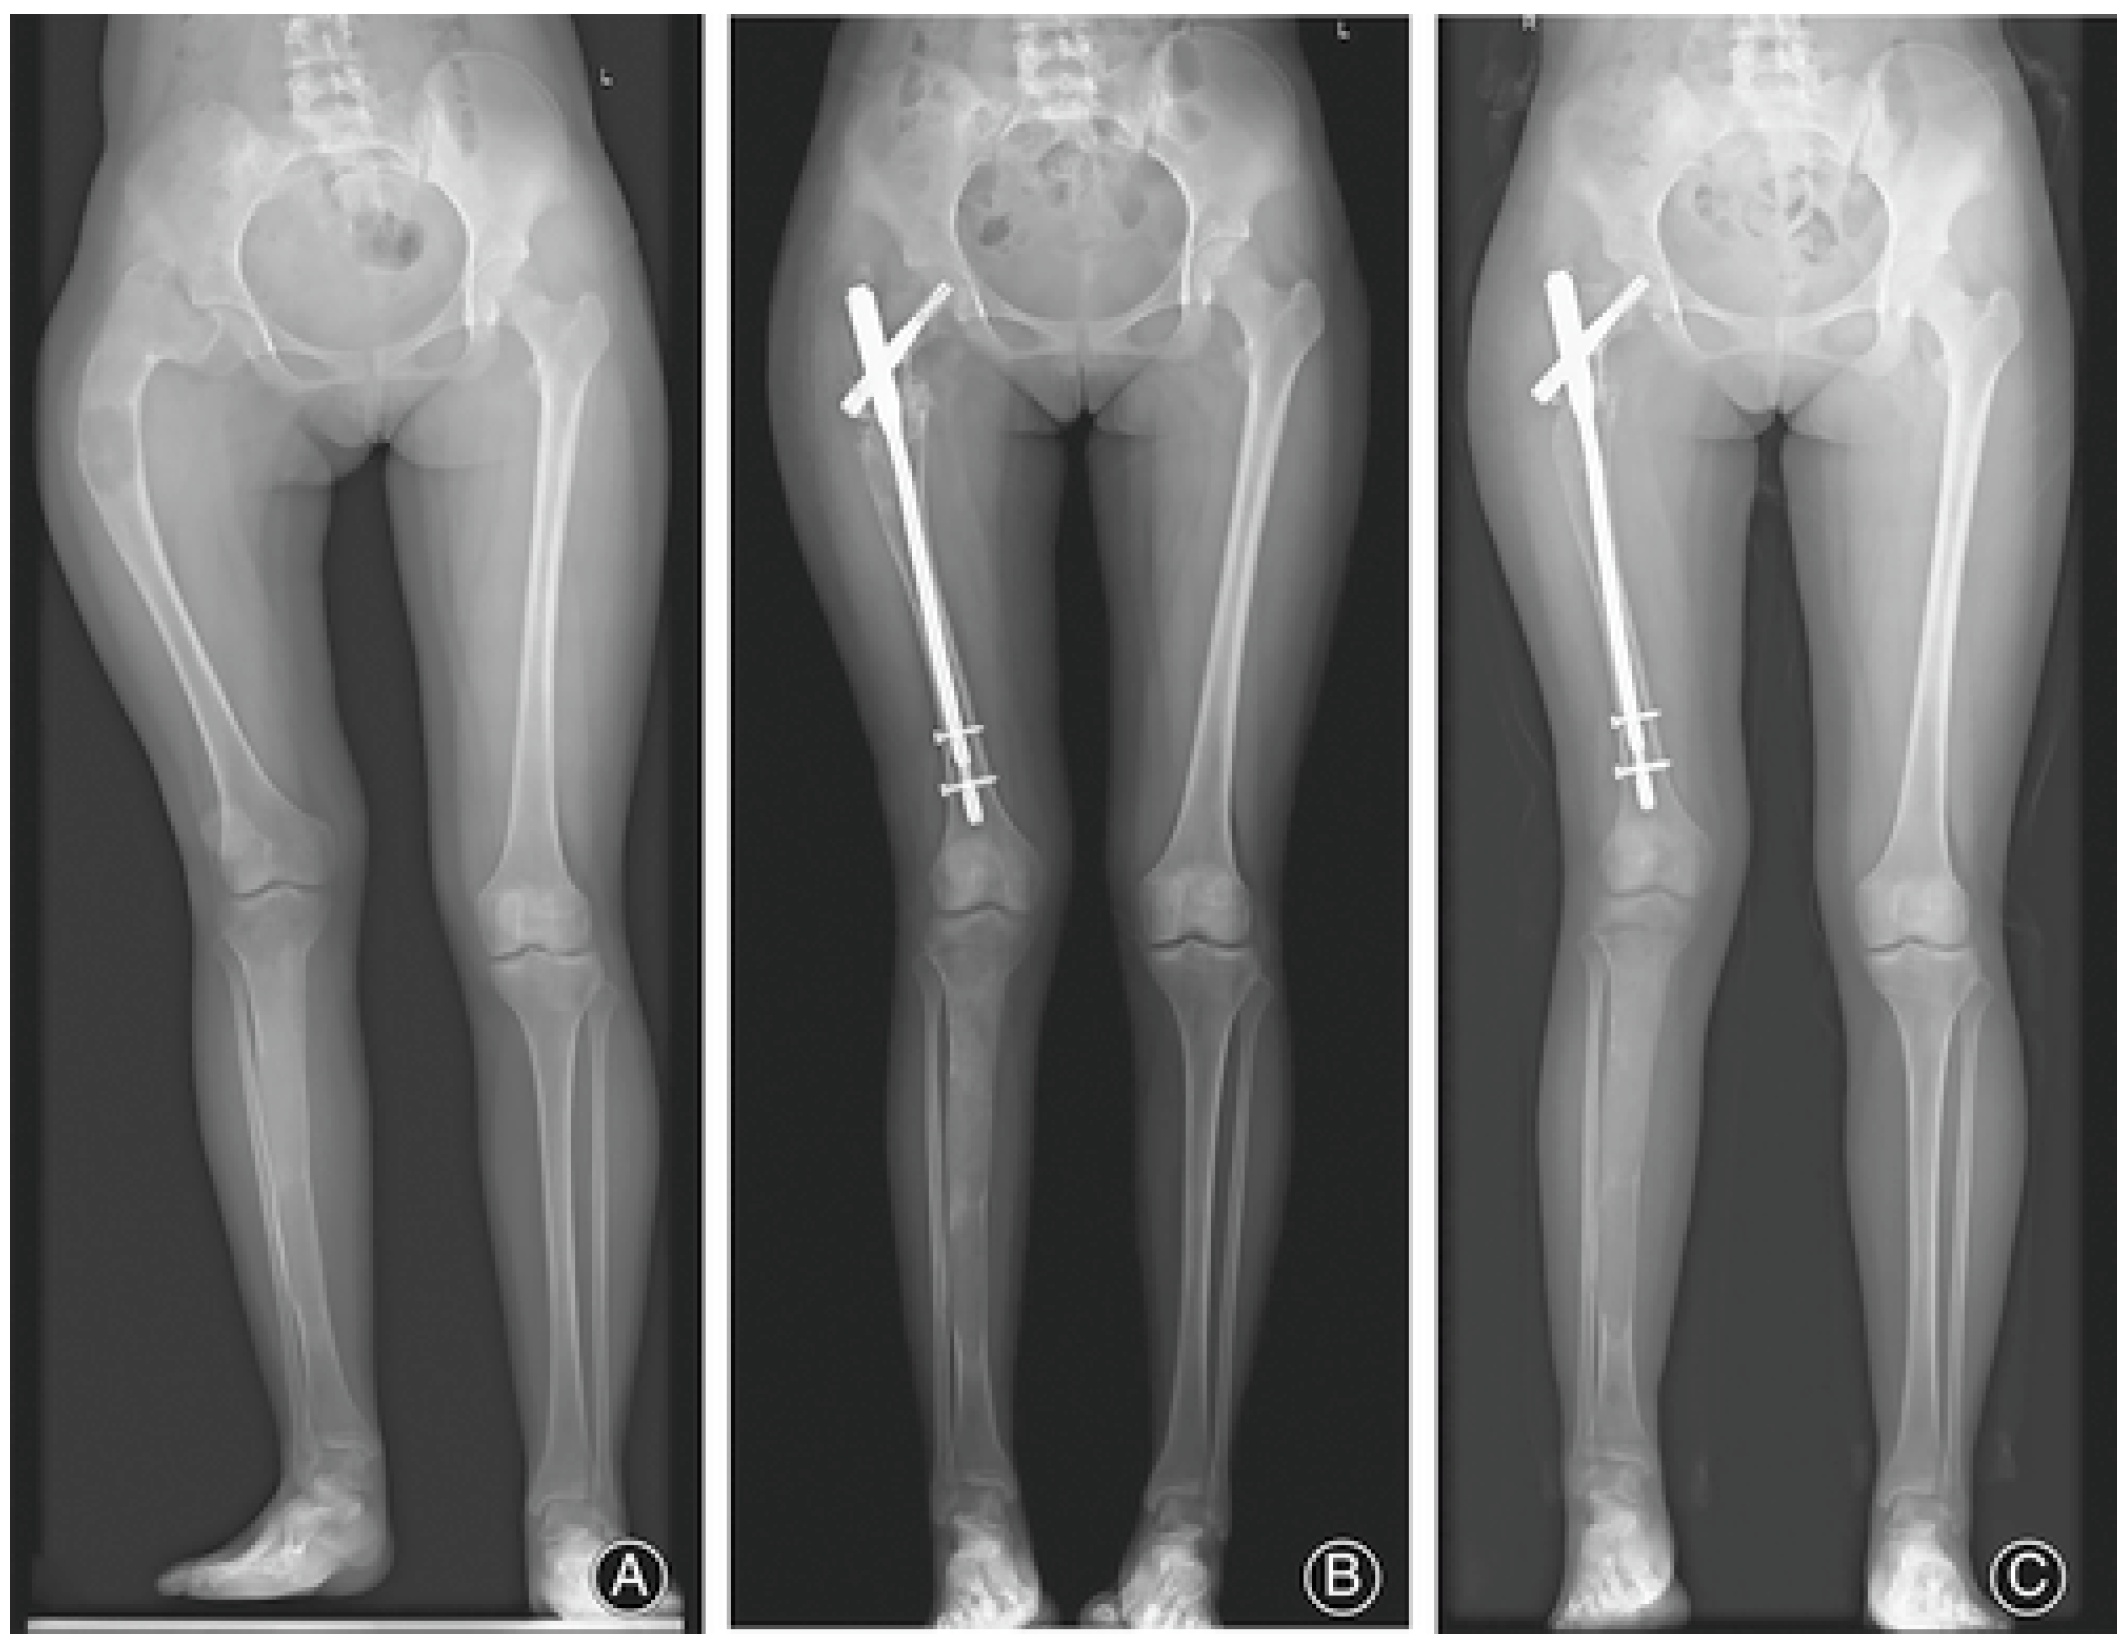

3.1. Appendicular Manifestations of FD/MAS

- Wang, Y.; Luo, Y.; Min, L.; Zhou, Y.; Wang, J.; Zhang, Y.; Lu, M.; Duan, H.; Tu, C. The West China Hospital radiographic classification for fibrous dysplasia in femur and adjacent bones: A retrospective analysis of 205 patients. Orthop. Surg. 2022, 14, 2096–2108. [Google Scholar] [CrossRef]

- Zhang, X.; Chen, C.; Duan, H.; Tu, C. Radiographic classification and treatment of fibrous dysplasia of the proximal femur: 227 femurs with a mean follow-up of 6 years. J. Orthop. Surg. Res. 2015, 10, 171. [Google Scholar] [CrossRef]

- Ippolito, E.; Farsetti, P.; Boyce, A.M.; Corsi, A.; De Maio, F.; Collins, M.T. Radiographic classification of coronal plane femoral deformities in polyostotic fibrous dysplasia. Clin. Orthop. Relat. Res. 2014, 472, 1558–1567. [Google Scholar] [CrossRef]